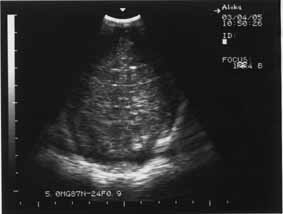

Кроме того, ишемический некроз проявляется повышением эхогенности обычно в острой фазе. В подострой и хронической фазах ведущую роль в диагностике играют неоднородность структуры, а также наличие участков с различной эхогенностью, в том числе кист. ПВЛ в подавляющем числе наблюдений является двусторонним процессом (рис. 1,2).

Рис. 1 Новорожденная Б 11 суток, СГ – 29 недель, ПВЛ III-IV степени на фоне повышенной эхогенности – мелкие анэхогенные образования (формирование кист). | Рис. 2. 10 суток, СГ – 30 недель, ПВЛ III степени, гиперэхогенность в перивентрикулярном пространстве (до образования кист). |

Эхографическое выявление острой фазы ПВЛ в первые сутки жизни может быть затруднительным. Это обстоятельство диктует необходимость динамического эхографического наблюдения за недоношенными детьми независимо от наличия или отсутствия у них морфологической картины поражения ЦНС в первые трое или даже семь суток жизни. С момента начала некротического процесса в веществе мозга до образования кисты обычно проходит 10-14 дней (рис.1,2). Во всех случаях перивентрикулярный некроз со временем приводит к пассивной внутренней гидроцефалии, которая может развиться через 2-3 недели после рождения.